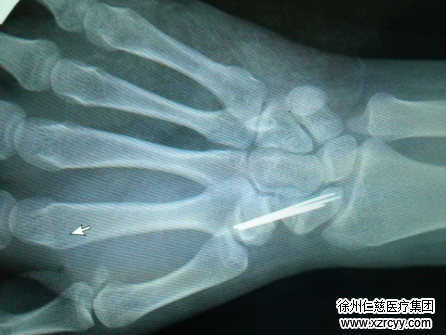

7月12日,我院手外科专家朱辉、齐伟亚联手为小光进行了“关节镜下的植骨内固定术”,经过近4个小时的精心手术,小光右腕舟状骨骨折得以成功修复。因为是关节镜下的微创手术,创伤小、恢复也相当快,术后几天后,折磨小光足足7个月之久的手腕疼痛终于消失了。

据必威官方首页官网betway手足显微外科二病区主任齐伟亚介绍,腕舟状骨骨折因其形状细长似舟故得名,是腕部常见的骨折,也是最易被忽视的骨折之一,多发生于体育活动及车祸中,发生机制多为腕关节背伸着地。当腕背伸桡偏位着地时,地面冲击力由舟状骨远端向上传导,桡骨远端关节面背侧缘及月骨正好托住舟骨,桡骨茎突在身体重力的作用下,对其腰部或远近端产生撞击以致其发生骨折。因其腰部细长,且多为受力部位,故最易发生骨折。